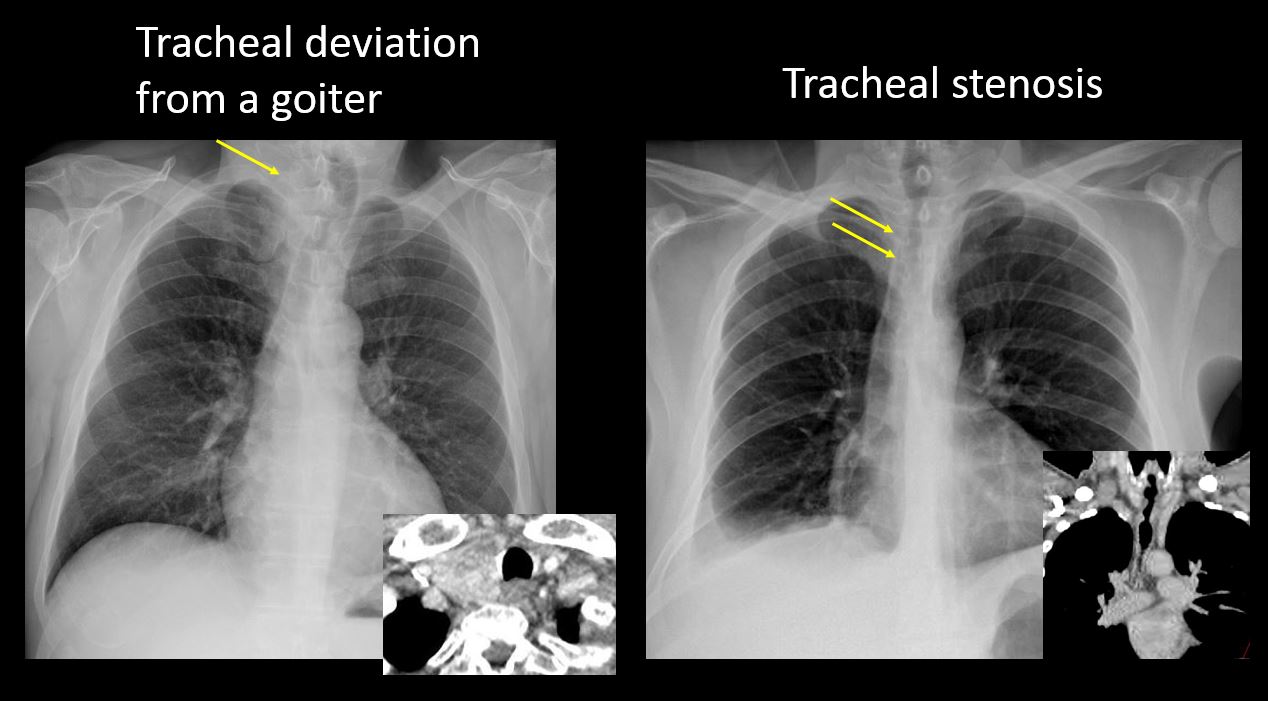

There is abnormal tracheal deviation or narrowing on the frontal and/or lateral view. |

No | NA |

The superior mediastinum is abnormally widened considering the technique. |

There is abnormal shift of the mediastinum. |